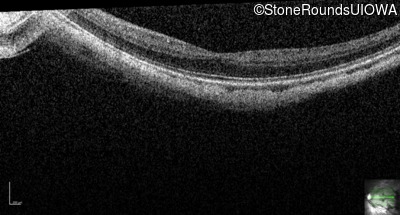

Age at visit: 25 years

OD OS